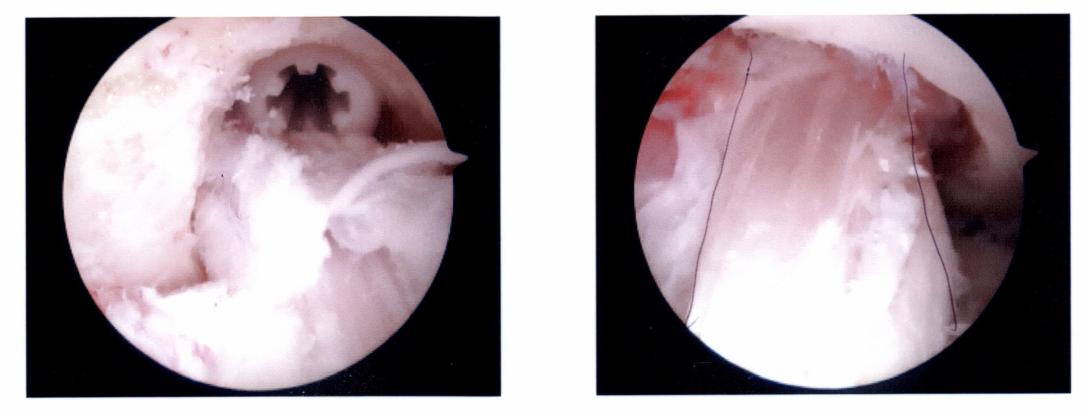

Two are above, I’ll spare you all the others as I couldn’t really tell you what in the world we would be looking at. I was actually quite impressed that he was able to do this all through one little incision.

The left photo shows the calcium screw and the right photo shows the pateller tendon installed in it’s new location as my new ACL.